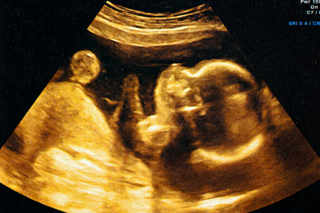

La pré-éclampsie touche entre 5 et 8 % des femmes enceintes. Si cette complication est bien suivie en Suisse, elle reste une des trois causes de mortalité pour les femmes et les nourrissons dans le monde. Une étude de lʹEcole polytechnique de Zurich (EPFZ) sʹest penchée sur les causes de cette maladie.

Cécile Guérin se penche sur une intervention particulière et très délicate: l'opération in utero sur des fœtus.